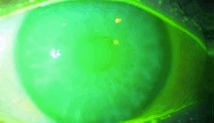

淚膜破裂時(shí)間測(cè)定:

1、角膜熒光素納染色

2、計(jì)算淚膜破裂時(shí)間